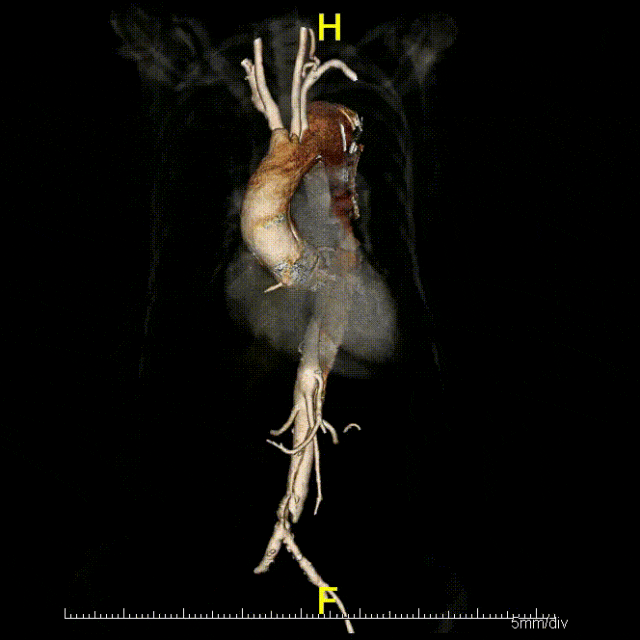

【根部挑战】带瓣腔内修复的前沿探索

目前专家共识的一个重要遗憾是未涉及根部夹层的带瓣腔内修复。主动脉根部夹层常合并瓣膜撕裂、瘤样扩张等问题,传统治疗面临巨大挑战。针对这一难题,研究团队提出瓣窗型腔内移植物对根部夹层腔内治疗,已获得上海市科委启明星计划(40万)、上海市卫健委新兴前沿技术(100万)、上海市科委重点项目(100万)等多项基金支持,累计经费超200万元。

2020年,团队首次报道成功的主动脉根部腔内重建动物实验,发表于JACC(IF=20.6)。实验结果显示:手术时间控制在1小时内,术后第2天动物可自行进食,长期存活率达97.2%。这一突破为未来临床转化奠定了坚实基础

针对升主动脉根部病变,目前有两条技术发展路径:

路径一:Off-label PMEG(经导管瓣膜增强移植物)

路径二:专用腔内移植物研发

国际上,欧美先锋术者已率先施行成功的“ENDO BENTALL”手术,采用双向入路(Rendez-vous access),虽无需改装移植物,但存在循环崩溃风险,需ECMO支持,且有心尖入路相关风险。新的专用器具也在国外研发中。